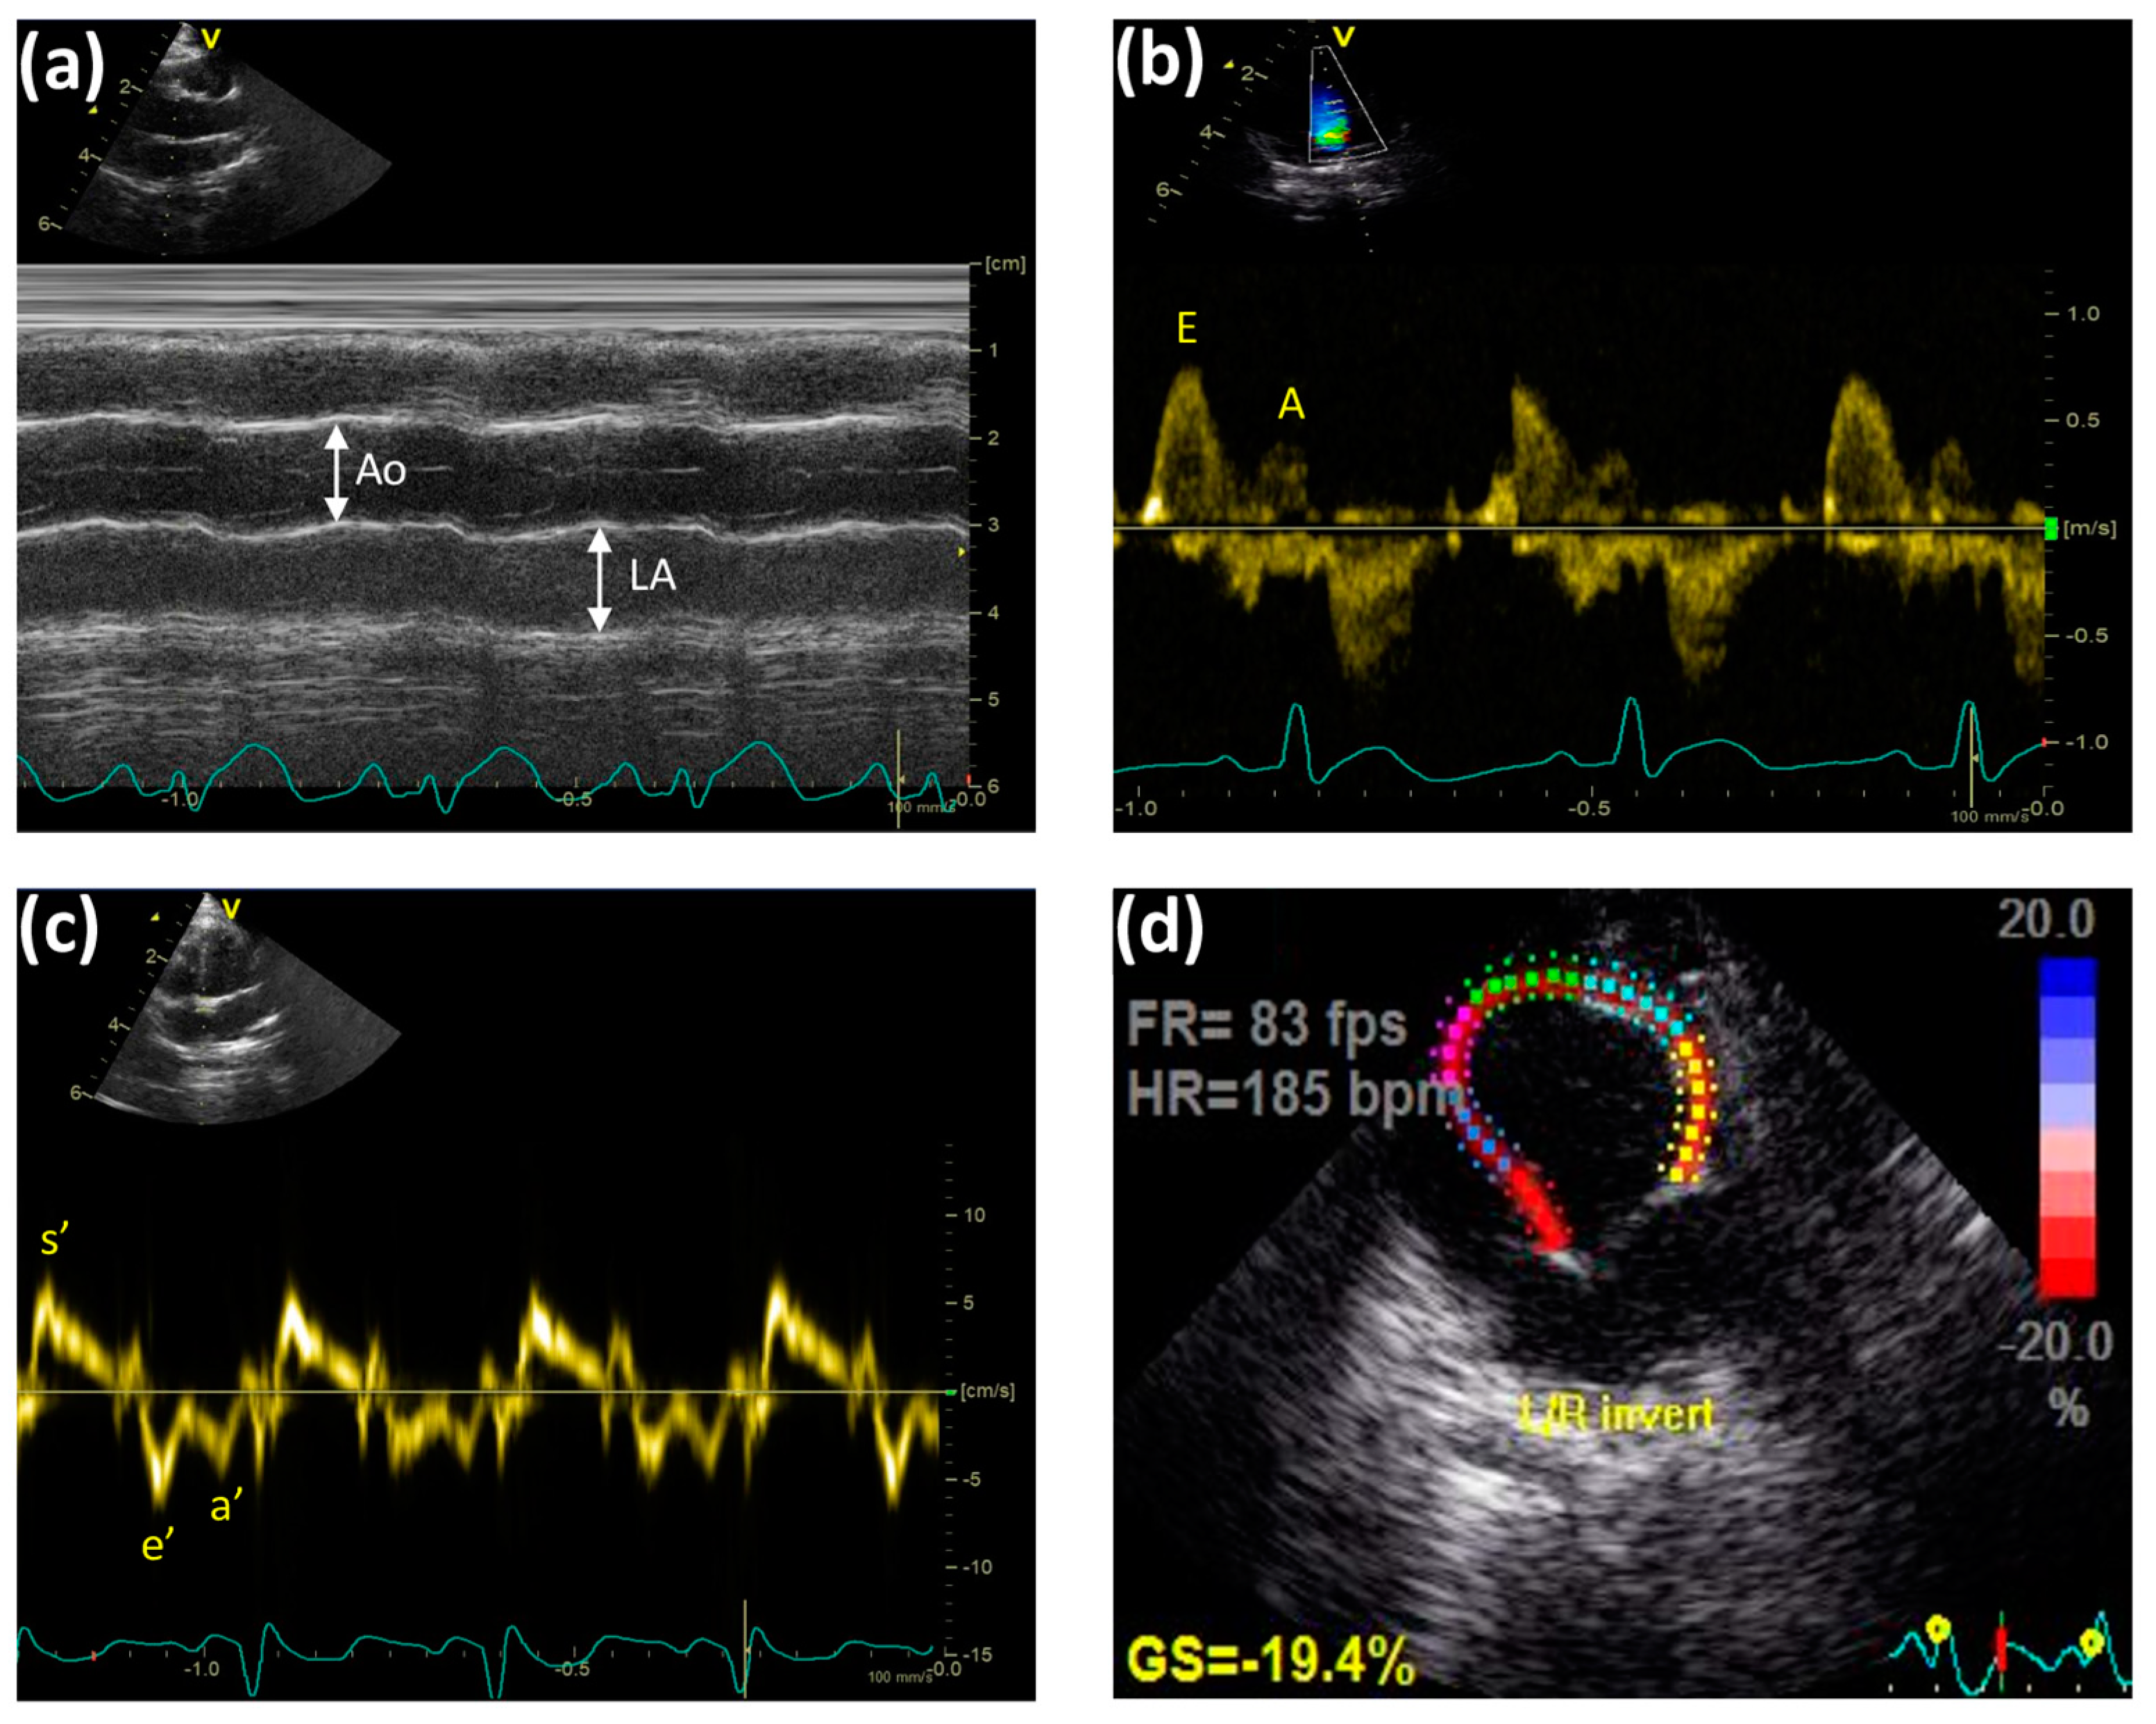

2.3. Atherosclerosis-Associated Cardiac Dysfunction Was Attenuated by Anthocyanin Administration

4.5. Transthoracic Echocardiographic Technique

- Nagueh, S.F.; Smiseth, O.A.; Appleton, C.P.; Byrd, B.F., 3rd; Dokainish, H.; Edvardsen, T.; Flachskampf, F.A.; Gillebert, T.C.; Klein, A.L.; Lancellotti, P.; et al. Recommendations for the Evaluation of Left Ventricular Diastolic Function by Echocardiography: An Update from the American Society of Echocardiography and the European Association of Cardiovascular Imaging. J. Am. Soc. Echocardiogr. 2016, 29, 277–314. [Google Scholar] [CrossRef]

- Sharifov, O.F.; Schiros, C.G.; Aban, I.; Denney, T.S.; Gupta, H. Diagnostic Accuracy of Tissue Doppler Index E/e’ for Evaluating Left Ventricular Filling Pressure and Diastolic Dysfunction/Heart Failure With Preserved Ejection Fraction: A Systematic Review and Meta-Analysis. J. Am. Heart Assoc. 2016, 5, e002530. [Google Scholar] [CrossRef] [PubMed]

- Douglas, P.S. The left atrium: A biomarker of chronic diastolic dysfunction and cardiovascular disease risk. J. Am. Coll. Cardiol. 2003, 42, 1206–1207. [Google Scholar] [CrossRef] [PubMed]

- Bruch, C.; Schmermund, A.; Dagres, N.; Katz, M.; Bartel, T.; Erbel, R. Tei-Index in coronary artery disease--validation in patients with overall cardiac and isolated diastolic dysfunction. Z. Kardiol. 2002, 91, 472–480. [Google Scholar] [CrossRef]